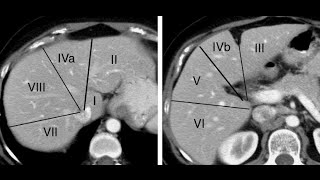

TC do abdome.  Segmentação hepática

5:59

Jezreel

63,388 views